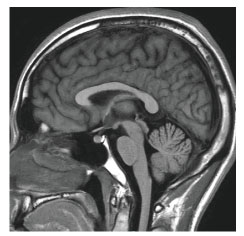

MRI(Magnetic Resonance Imaging:磁気共鳴画像診断装置)検査は、強力な磁石でできた円筒状の機械に入り、磁気や電波の力を利用して体の断面や血管を撮影する検査です。

当院のMRI画像集